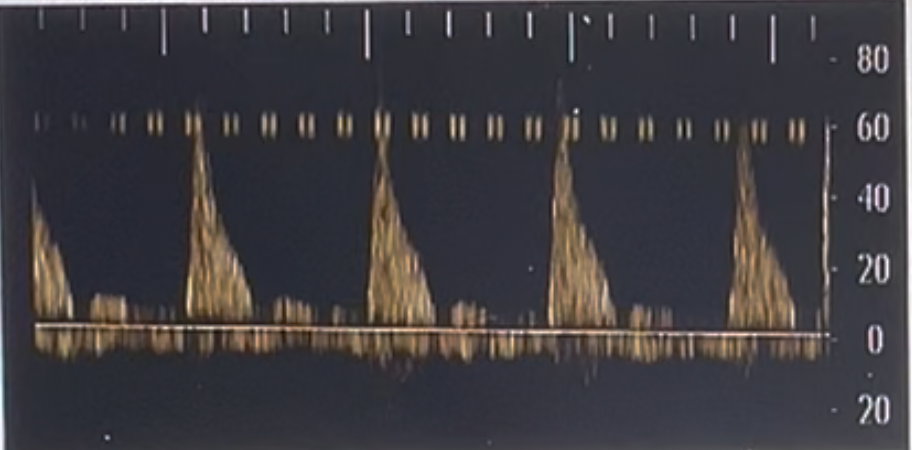

Where does the first caliper go when measuring the acceleration time on PW Doppler? Use your mouse to position the cursor over the correct part of the 3rd waveform and click to set your answer.

blue/green